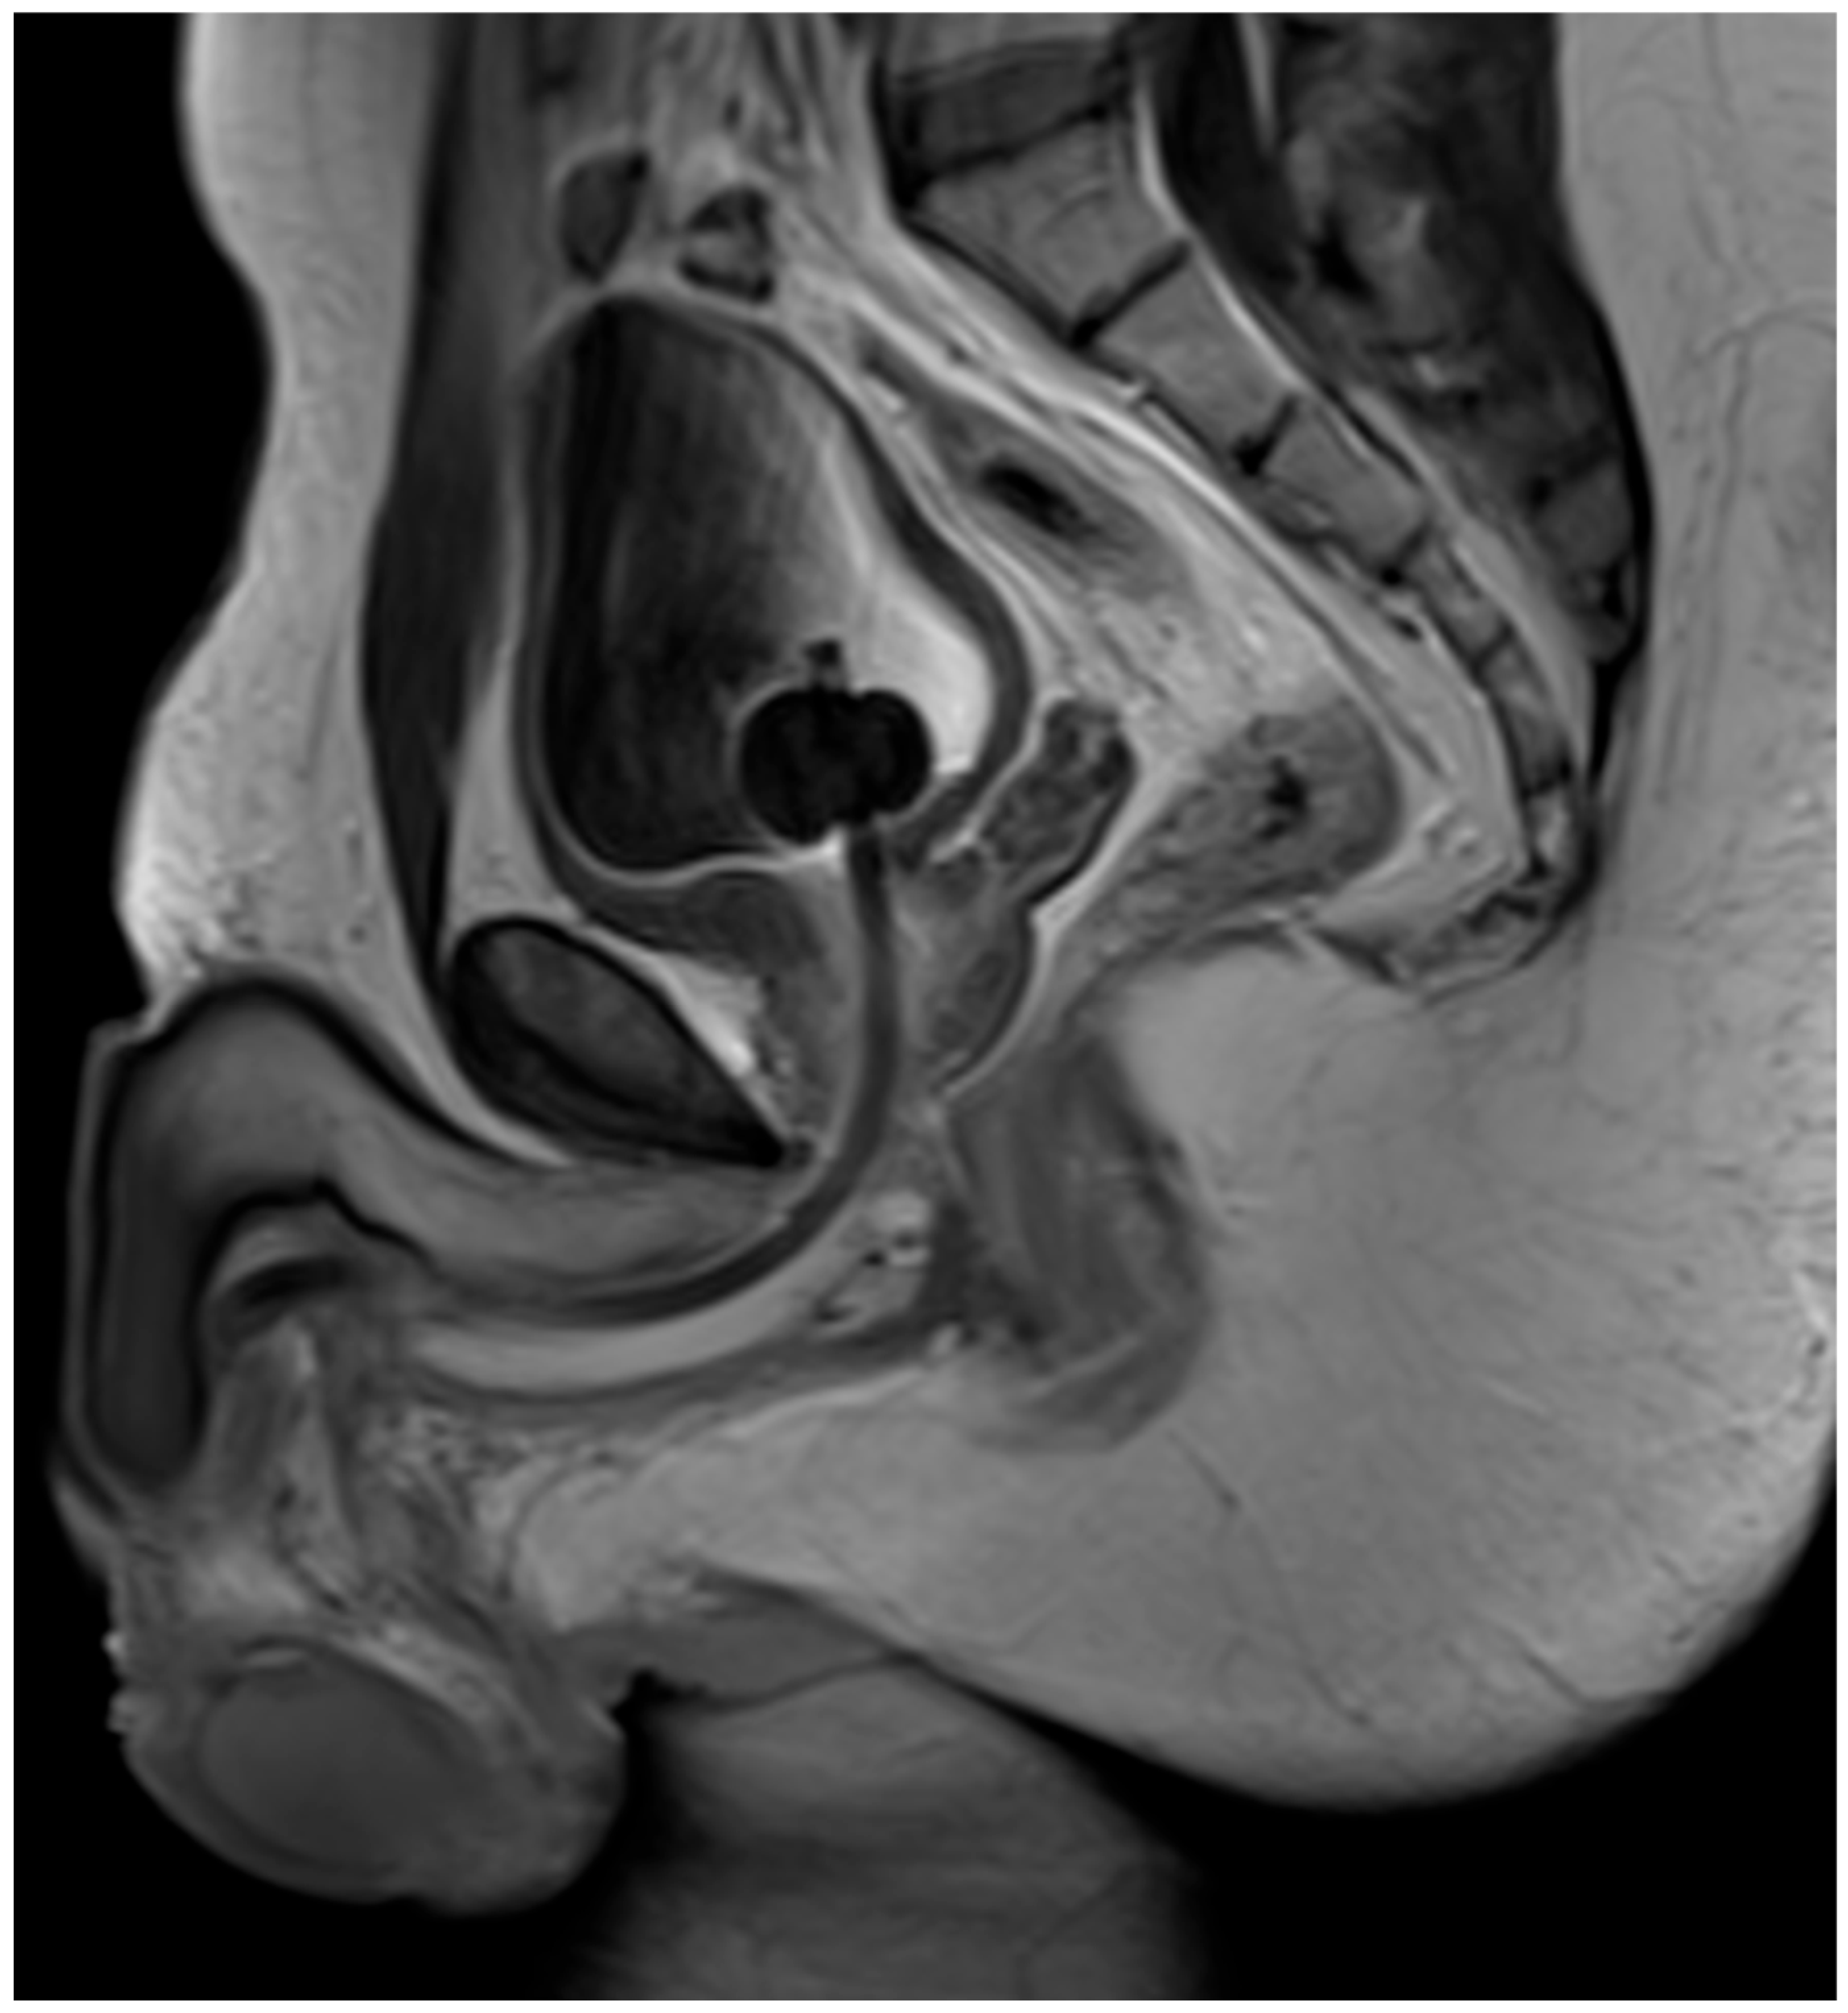

4. Case Report